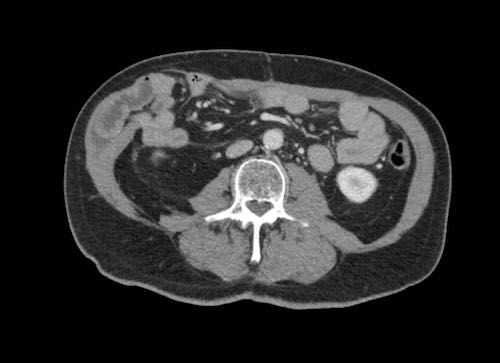

Hình ảnh CT của một bệnh nhân ung thư phúc mạc.

Một lượng nhỏ dịch cổ trướng hiện diện ở góc phần tư trước bên phải.

Các đường dày dạng nốt vuông góc với thành ruột được ghi nhận.

Hình ảnh này đại diện cho tổn thương xâm lấn mạc treo ruột lan rộng (mũi tên).